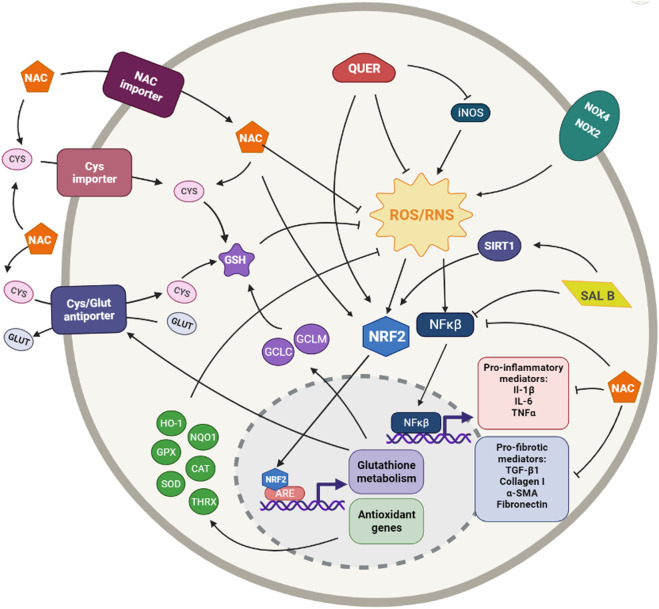

Свързаният с ядрото еритроид фактор-2 (Nrf2) предизвиква експресията на повечето от антиоксидантните и детоксикиращите ензими, поради което той е от съществено значение за активиране на антиоксидантната защитна система.

В отговор на стресови сигнали Nrf2 се освобождава и се премества в ядрото, където предизвиква проявата на стотици антиоксидантни гени. Освен това Nrf2 регулира експресията на гени, участващи във възпалителни и фибротични реакции [11].

1. N-ацетил цистеин (NAC) е аминокиселина, получена от л-цистеин, с мощна редукционна способност. Този аминотиол е не само прекурсор на глутатиона (GSH), но също така има пряка способност за улавяне на ROS и може да индуцира експресията на свързания с ядрото еритроид фактор-2 (Nrf2) [32, 33,34]. Тези свойства са превърнали NAC в широко използван мощен антиоксидант. (Фигура 1)

2. Антиоксидантът кверцетин е полифенолен растителен флавоноид, който присъства повсеместно в зеленчуците и плодовете, както и в чая и червеното вино [42,43].

Той е мощен директен уловител на ROS, но също така индиректно упражнява антиоксидантната си функция чрез активиране на пътя Nrf2 и индуциране на регулирани от Nrf2 гени, като NQO1, HO-1, GPX1 и т.н. [44]. Кверцетинът обаче има не само силен антиоксидантен, но и противовъзпалителен капацитет [45].

3. Салвианолова киселина В (Sal B) е една от най-активните фенолни киселини, извлечени от Salvia miltiorrhiza, Danshen. Тя показва силна антиоксидантна, противовъзпалителна, антифибротична и антиапоптотична способност [49]. Тя може да упражнява антиоксидантните си ефекти чрез директно отстраняване на ROS или чрез увеличаване на експресията на различни антиоксидантни ензими, като SOD, GPx и HO-1, или инхибиране на експресията на Nox2 и Nox4; като регулирането на пътя Nrf2 е основната цел на тези антиоксидантни механизми [50].